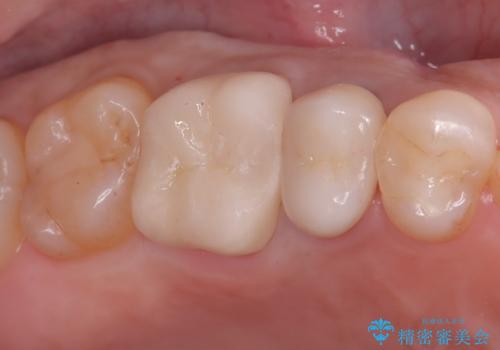

治療では、まず古い銀歯を慎重に取り外し、内部の虫歯の有無を確認しました。その後、残っている歯質を保護し、強度を高めるために、適合性に優れたオールセラミッククラウンを作製・装着しました。

セラミッククラウンは、

強度: 歯全体を覆うため、咬合力による歯への負担を分散させ、破折リスクを大幅に軽減します。

審美性: 天然歯に近い透明感と色調を持つため、銀歯の時と比べて格段に自然で美しい見た目になります。